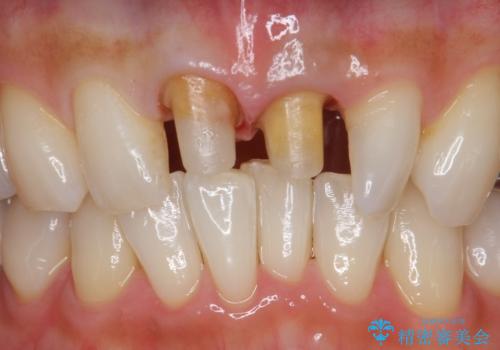

- 前歯の変色とガタつきがきになるとのことで来院されました。

矯正治療の希望はなかったため、セラミッククラウンで被せて治療していくことになりました。

元々根管治療がされていたにも関わらず被せ物が作られておらず、このままではどんどん変色が進んでいってしまう状態でした。

歯をある程度削ることにはなりますが、被せ物にすることで歯の変色を隠し短期間でキレイな口元に仕上げることができました。